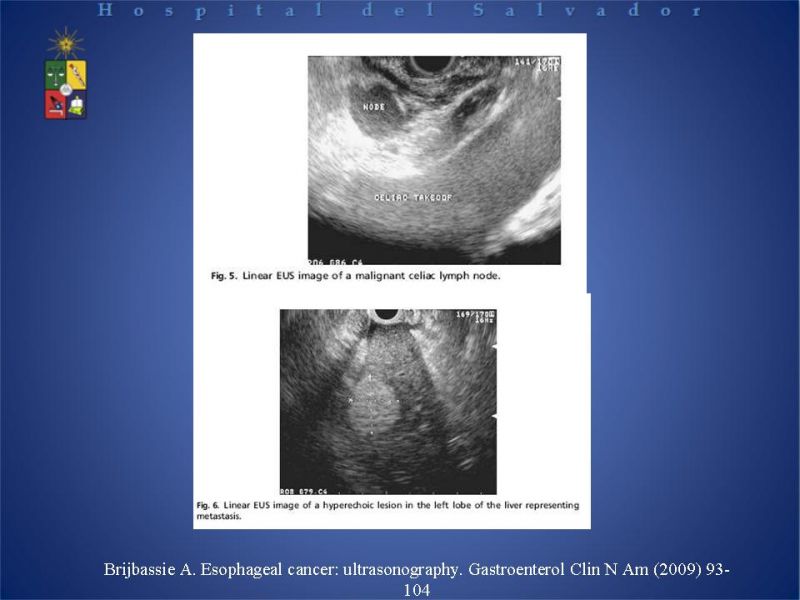

Cáncer de Esófago

Digestivo Alto

| Autor: Dr. Alejandro Tapia Duhalde